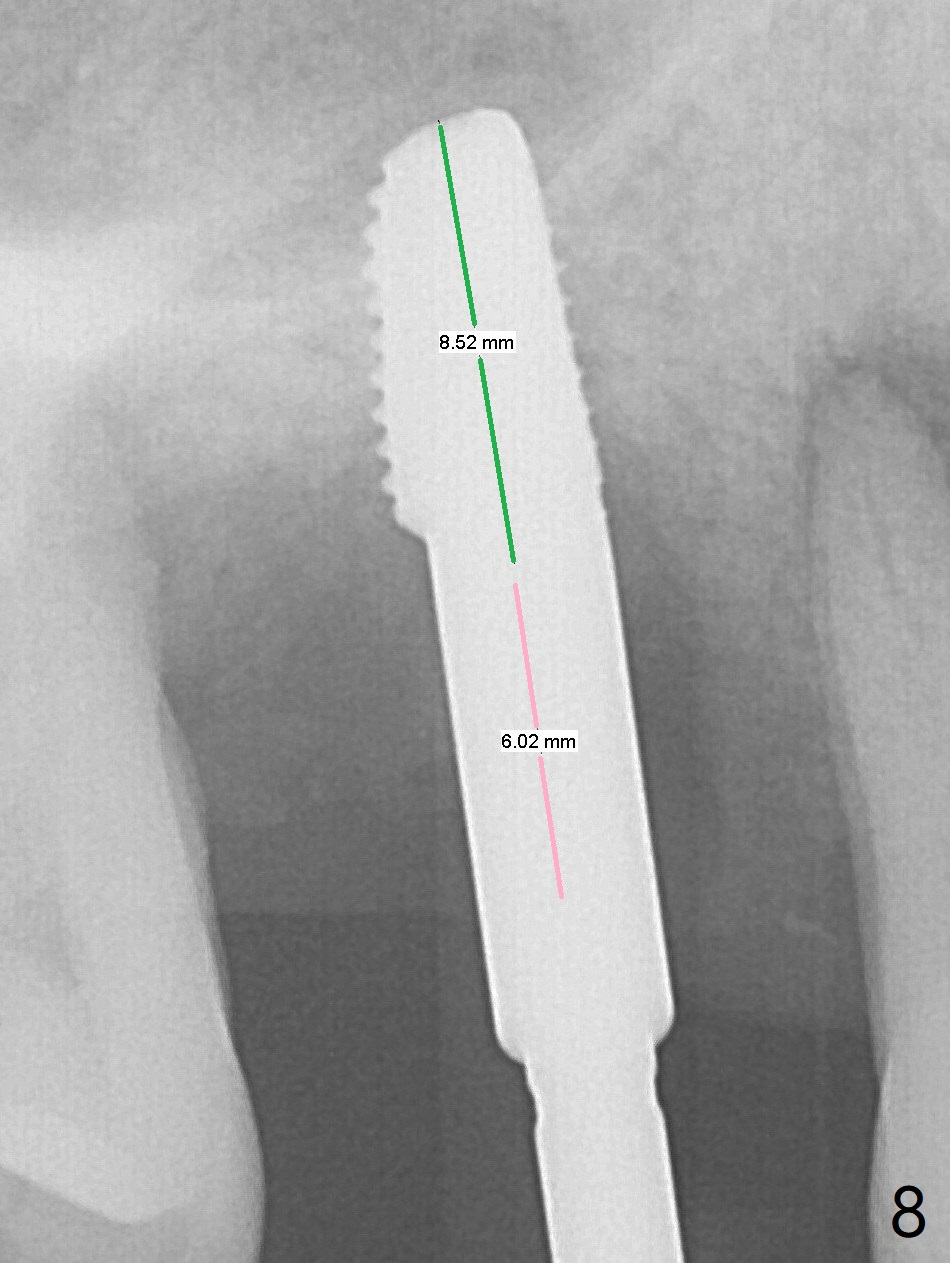

The tooth #3 has gingival recession moderate buccally (Fig.1) and severe palatally (Fig.2 P). The remaining bone height is estimated 4 mm (Fig.3). After extraction and debridement, the 3 sockets are packed with 2% Lidocaine 1:50,000 Epinephrine saturated gauze (Fig.4). When the gauze is removed from the buccal sockets (Fig.5 black area), the buccal portion (B) of the septal gingiva (*) is sectioned from the buccal gingiva (Fig.6 curved white line) and elevated from the underlying septal bone and pushed palatally (arrow). The septal gingiva (including the buccal portion) will be the palatal soft tissue wall of the subsequent osteotomy, providing blood supply to allograft to be placed. In short, the septum (through the buccal socket) will be the osteotomy site.

Initial osteotomy depth is 4 mm (Fig.7). The sinus membrane is found to be perforated when the depth increases to 8 mm. The latter could be prevented by taking CT and/or using osteotome. The subsequent osteotomy depth is 5 mm until 4.0 mm in diameter. When the 4.5 mm tap is inserted with initial stability, the shortest implant (8.5 mm, Fig.8 green) will be partially protruded into the sinus and partially exposed in the socket and the cuff of the abutment is expected to be around 6 mm (pink). Since the 5 mm tap achieves primary stability, a 5x8.5 mm implant (following placement of Osteogen plug to repair the perforated sinus membrane) is placed at the level just mentioned (Fig.9). Vanilla Graft mixed with minimal autogenous bone is packed (Fig.10.11 *) before and after insertion of a 6.5x5(4) mm abutment. An immediate provisional as well as a piece of Osteogen plug is fabricated to close the socket gap. The provisional and the abutment are dislodged 1 month postop (Fig.12). The wound has healed. The abutment is reloaded without the provisional. The implant appears to osteointegrate 4.5 months postop (Fig.13); in addition the bone graft seems to have migrated toward the roots of the neighboring teeth (arrows).